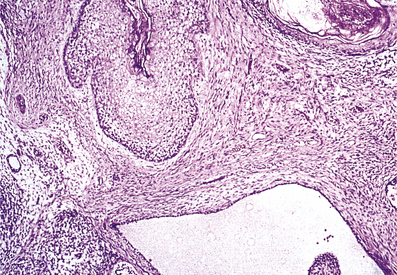

Balanitis xerotica obliterans

Balanitis xerotica obliterans is an uncommon penile lesion characterised by thickened white plaques and fissures on the glans and prepuce. The symptoms are of a non-retractile prepuce or preputial discharge, often necessitating circumcision. Similar lesions may develop around the urethral meatus with resulting scarring. The condition most commonly affects men aged 30–50 years.

The histological features are of hyperkeratosis and atrophy of the epidermis with basal layer degeneration. The papillary dermis shows hyalinisation of the collagen with an underlying infiltrate of lymphoid cells. Similar changes are seen in lichen sclerosus of the vulval skin; some people thus also refer to the penile lesion as lichen sclerosus.